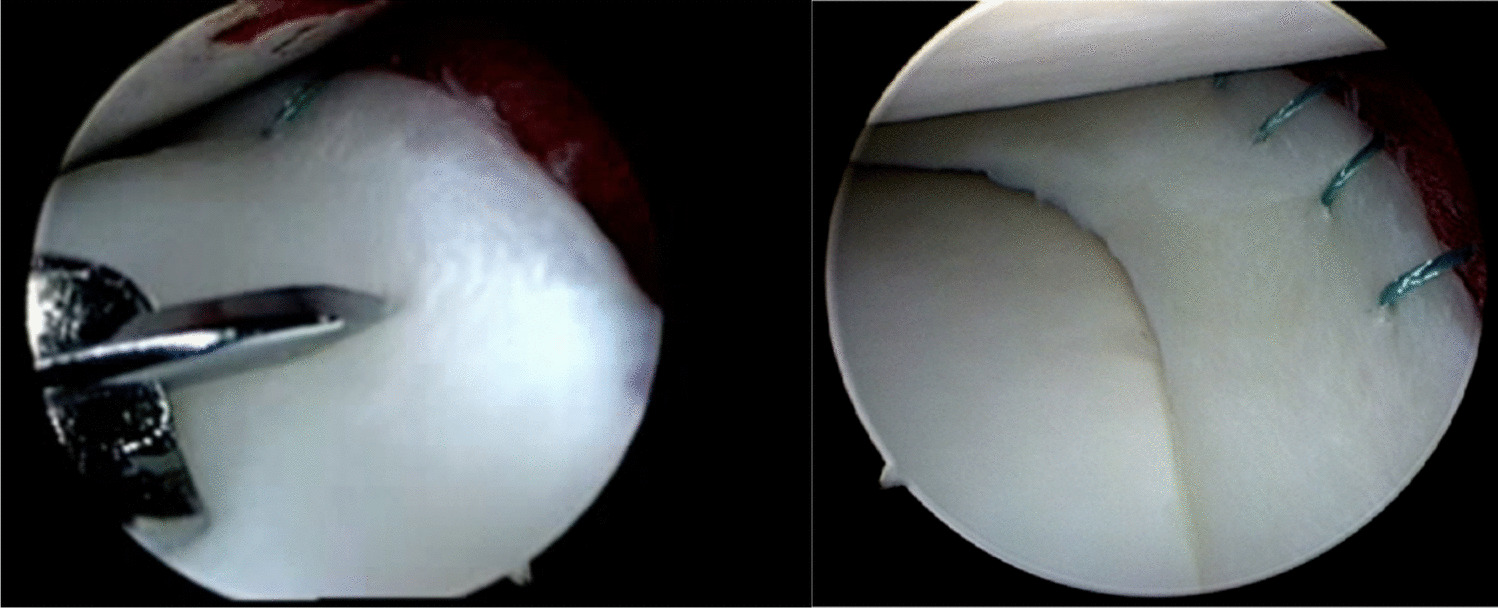

Imade S, Kumahashi N, Kuwata S, Kadowaki M, Ito S, Uchio Y. Clinical outcomes of revision meniscal repair: a case series. Am J Sports Med. 2014;42(2):350–7.

Krych AJ, Reardon P, Sousa P, Levy BA, Dahm DL, Stuart MJ. Clinical Outcomes After Revision Meniscus Repair. Arthroscopy. 2016;32(9):1831–7.